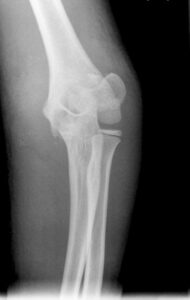

Doğumda dirsek eklemi tamamen kıkırdaktır ve radyografilerde bu kıkırdak alana bağlı olarak geniş radyolüsent bir alan görülür. Büyümeyle birlikte kemik dirseği oluşturacak ikincil kemikleşme noktaları ortaya çıkar. Düzgün radyolojik değerlendirmenin yapılabilmesi için bu kemikleşme noktalarının anatomik yapısı ve gelişiminin iyi bilinmesi gereklidir.

Bu noktaların ortaya çıkma zamanı tahmin edilebilir ancak hastadan hastaya, yaşa, cinsiyete, gelişime göre farklılık gösterebileceği unutulmamalıdır. Karşı taraftaki dirsekle karşılaştırılması patolojik görünüm ya da yapısal farklılığın ayırt edilmesinde yardımcı olur. Bu kemikleşme merkezlerinden ilk ortaya çıkanı Kapitulumdur. Ortaya çıkma sırasına göre “CRITOE” kısaltması kullanılabilir. Kapitulum hariç bu merkezler kızlarda erkeklere göre daha erken görülmektedir.